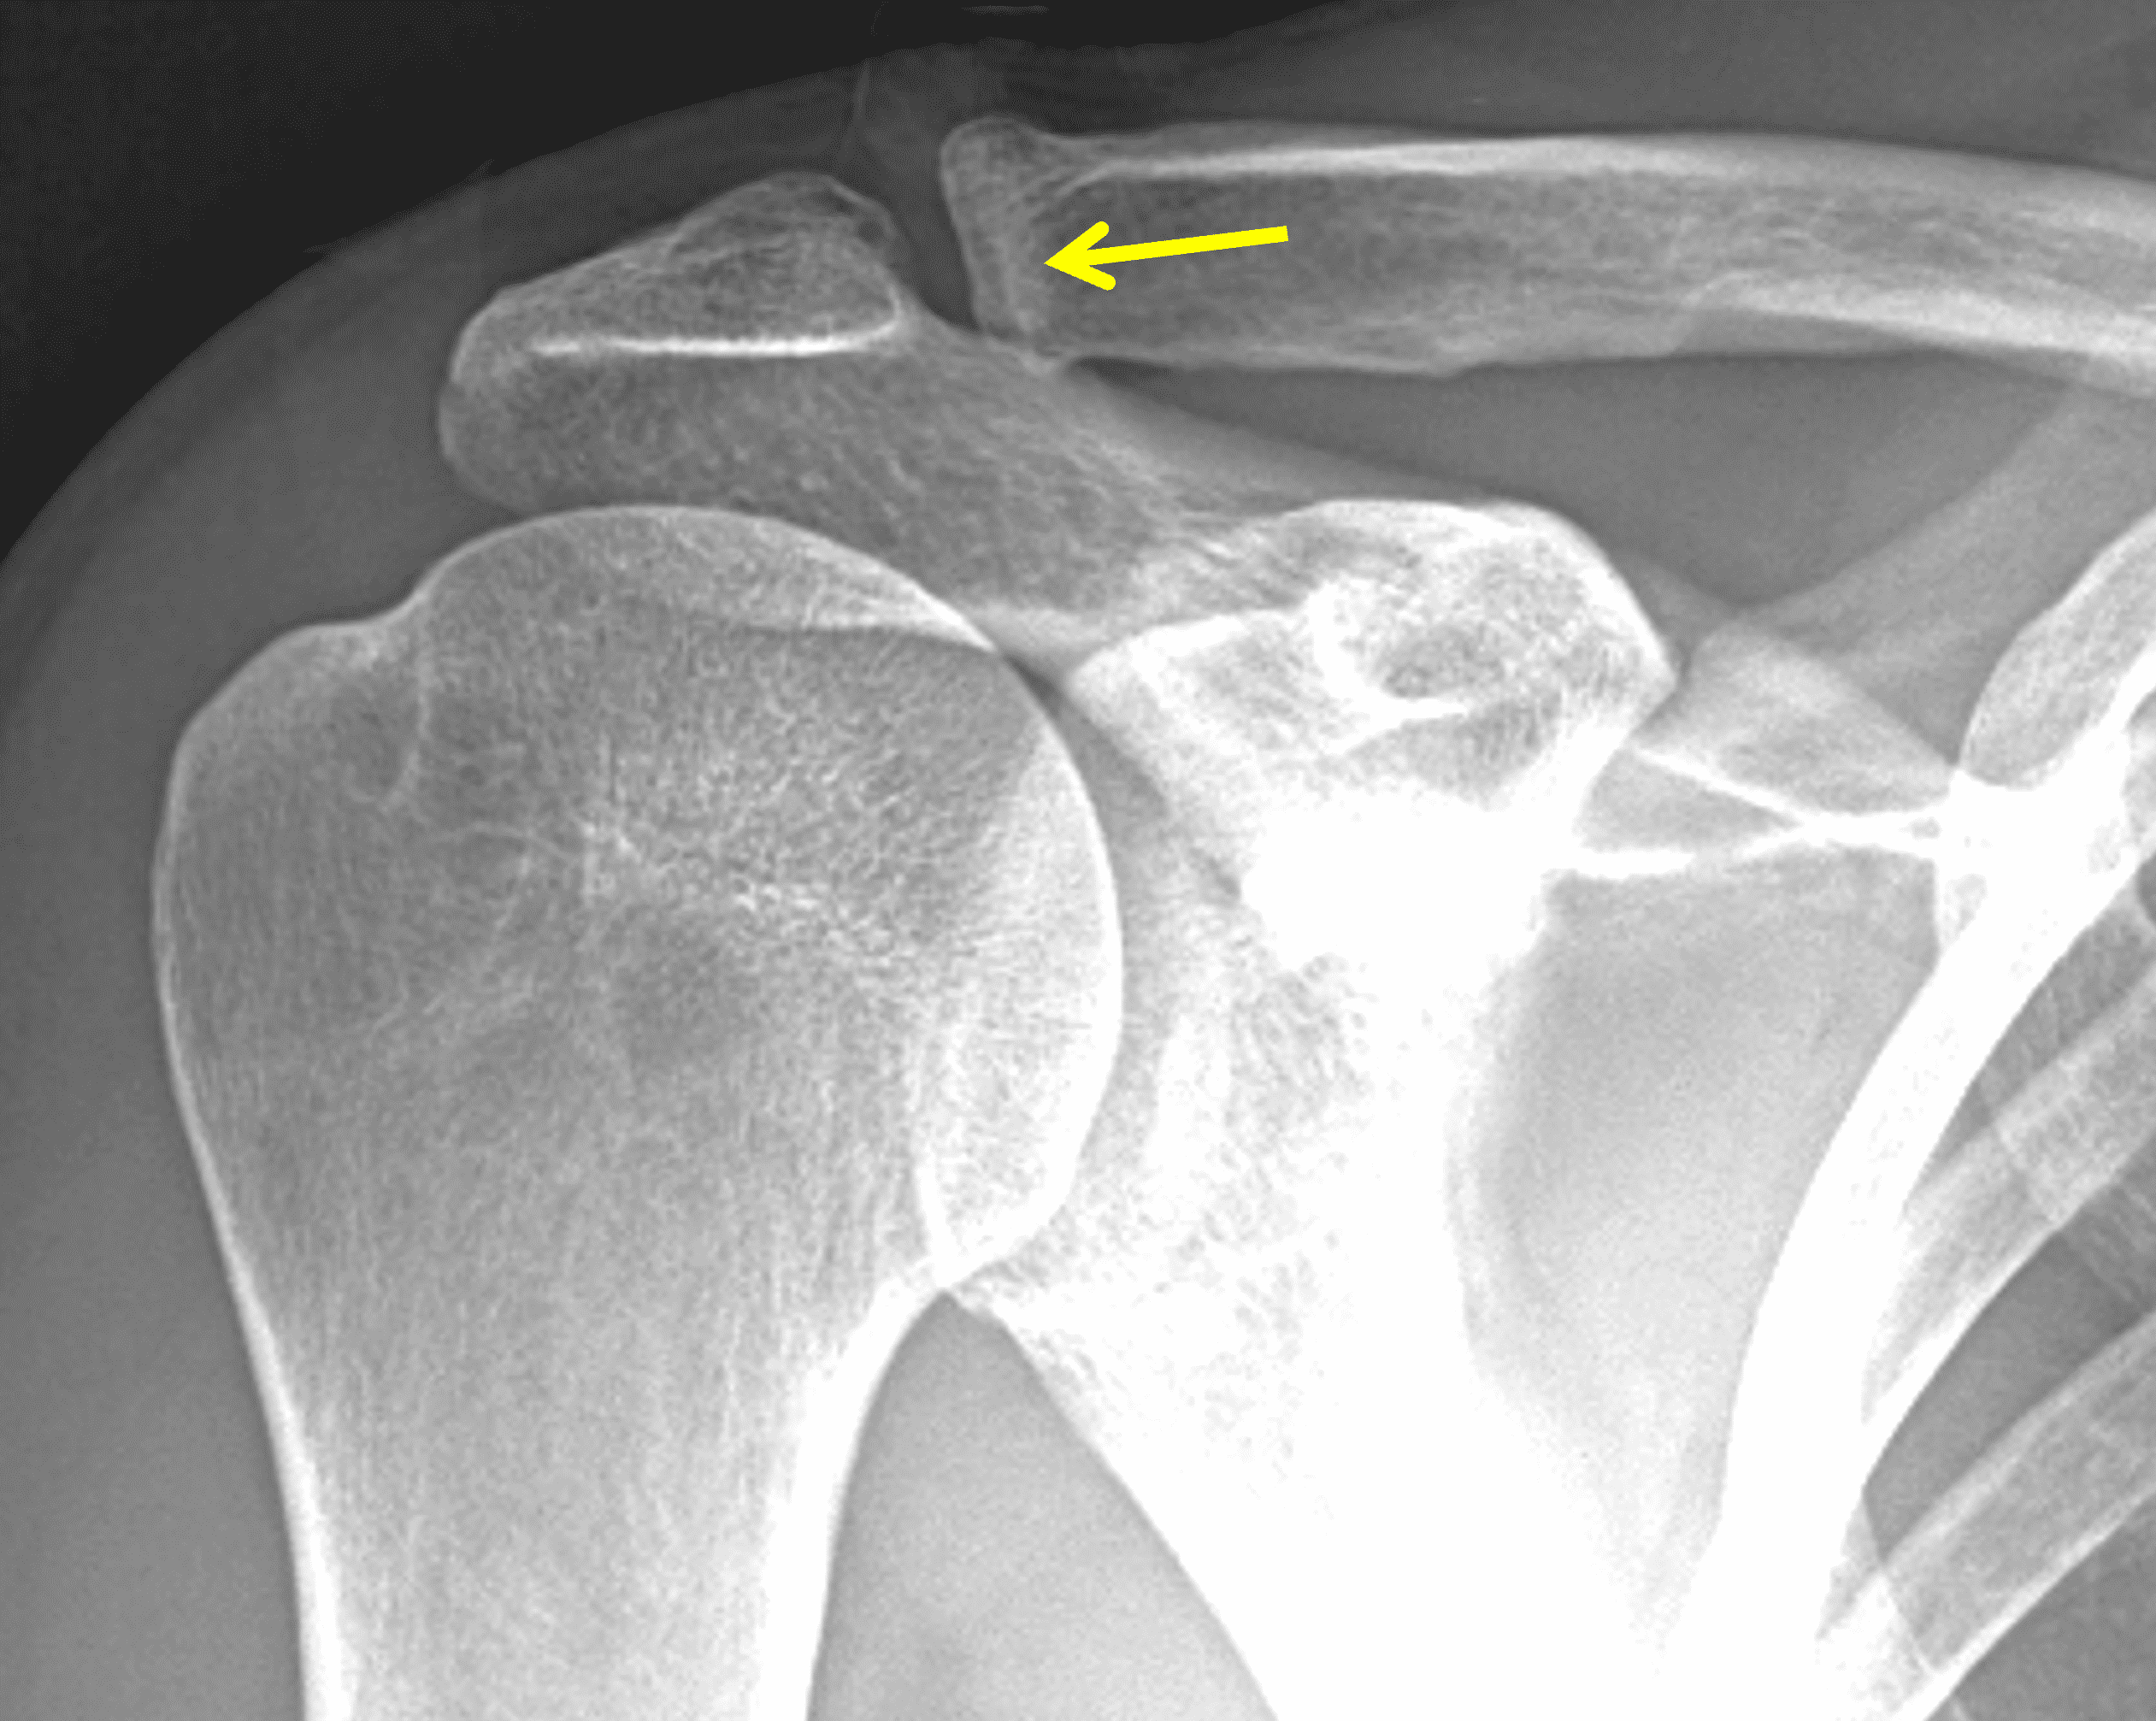

A 49-year-old male, avid weightlifter complains of chronic pain along the superior aspect of his right shoulder. He denies acute trauma. An AP radiograph (Figure 1A), as well as oblique coronal SPAIR (Figure 1B), axial fat-suppressed fluid sensitive (Figure 1C), and oblique sagittal T2-weighted images (Figure 1D) are shown. What are the findings? What is your diagnosis?

Radiographs: Initial radiographs may be normal or show features of other common unrelated AC joint pathology such as osteoarthritis. As inflammation and hyperemia in the distal clavicle progresses, bone density in the distal clavicle can decrease with indistinctness or discontinuity of the subchondral bone plate (Figure 3).  This so-called resorptive phase may also include frank erosions in the distal clavicle or a faint sclerotic line in the medullary space of the distal clavicle parallel to the bone end. Varying degrees of surrounding soft tissue swelling may be visible.  Later, during the late healing phase when symptoms have usually resolved, the distal clavicle may return to a normal radiographic appearance; a sclerotic line parallel to the distal bone end is visible after healing in some cases (Figure 4).  In patients with severe initial bone loss, re-cortication of the resorbed bone and erosions can occur leaving residual bone loss and contour defects in the distal clavicle. While it is typically not a primary modality for the diagnosis of DCO, CT demonstrates the same bone findings as radiographs.